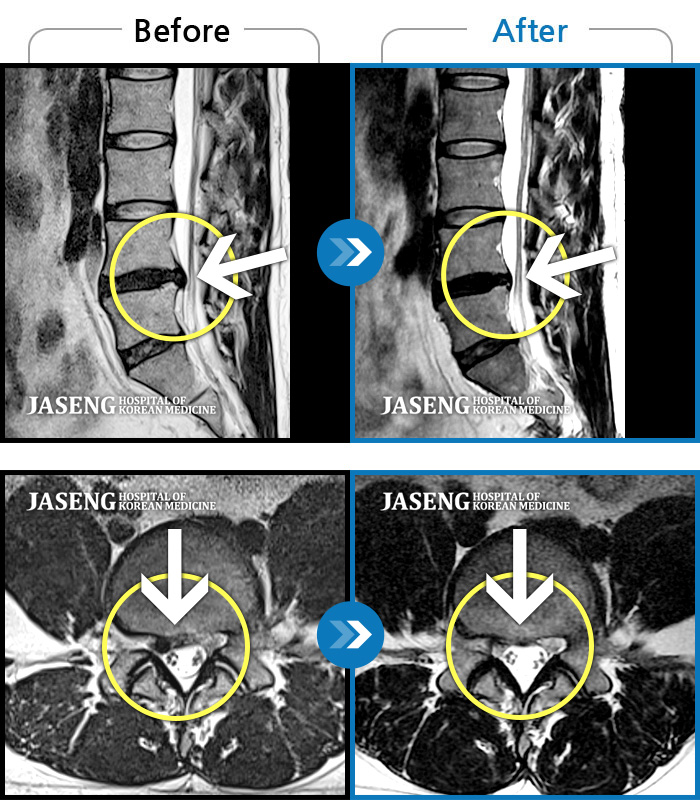

Before

After

환자에게 사전 동의를 받아 동일 조건에서 촬영되었습니다.

개인에 따라 치료 후 부작용이 발생할 수 있으니 의료진과 상담 후 치료를 진행하시기 바랍니다.

처음 내원 시 좌측 허리 뻐근한 통증과 좌측 허벅지부터 발가락까지 이어지는 당기고 저린 증상으로 보행까지 불편감 호소하시며 내원하신 환자입니다.